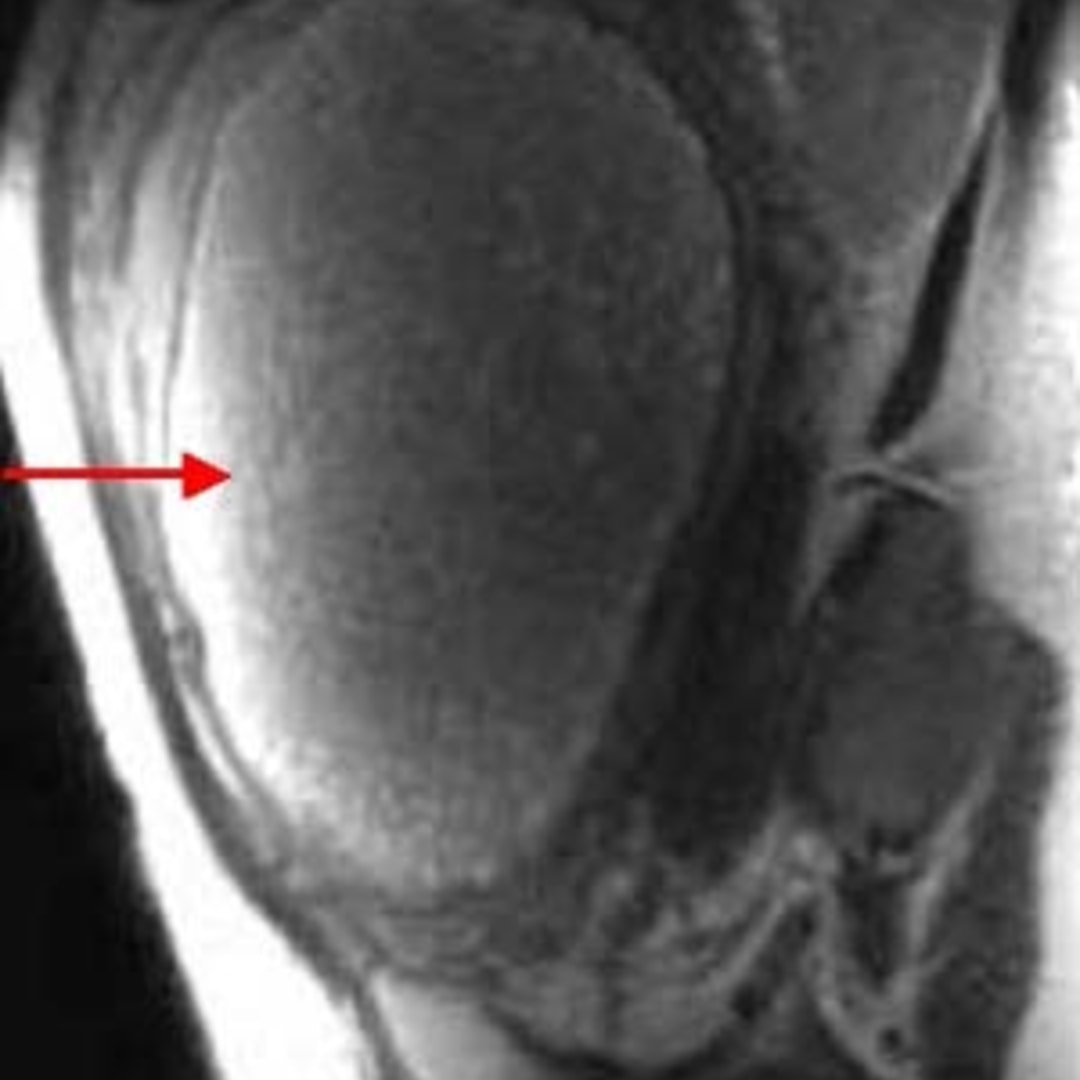

Invasive Molar Pregnancy And MRI: What Every Radiologist Must Know

Invasive molar pregnancy and MRI: What every radiologist must know www.semanticscholar.org

mri pregnancy molar invasive radiologist

molar mri invasive must radiologist know

mri molar pregnancy invasive radiologist

molar pregnancy invasive mri radiologist

invasive molar mri radiologist

molar pregnancy mri invasive radiologist